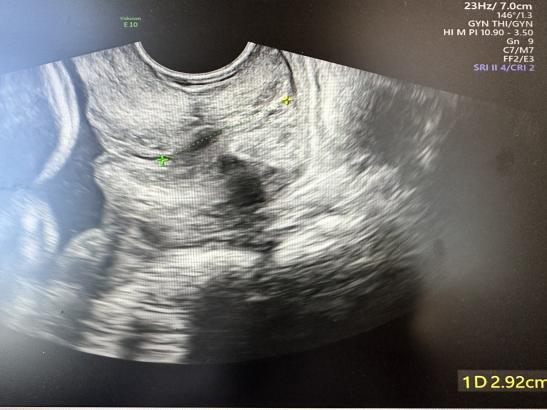

术前宫颈管内口至外口均分离呈U型

术后有效宫颈长度2.6cm